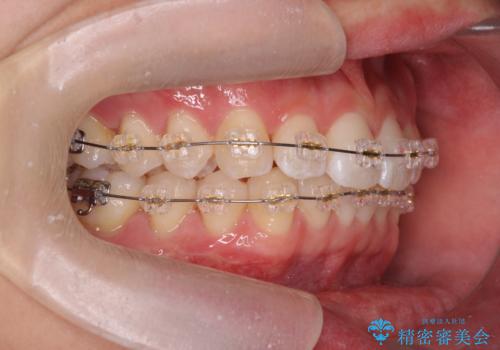

- 20代男性

- ワイヤー

- 10ヶ月

- 取り外しの必要なマウスピース矯正ではなくワイヤー矯正を希望され来院されました。

マウスピース矯正、ワイヤー矯正どちらの方法でも治療は可能ですが、ご要望の通りワイヤー矯正で歯の排列を行っていきます。